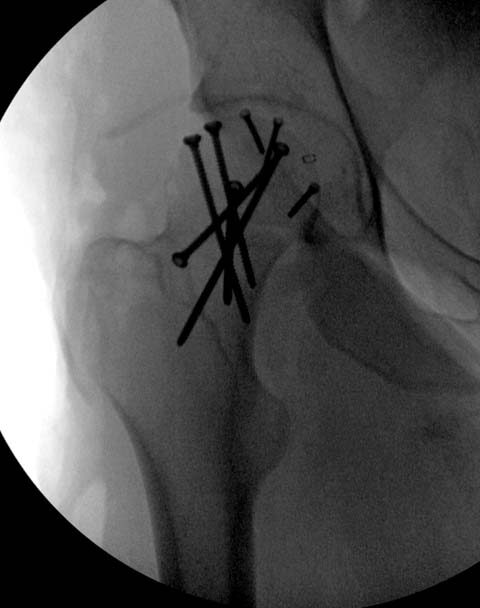

Здесь клинические примеры: Первый случай передний доступ, второй с ICP

monitor Flipp Trochanteris

и с переломом заднего края.